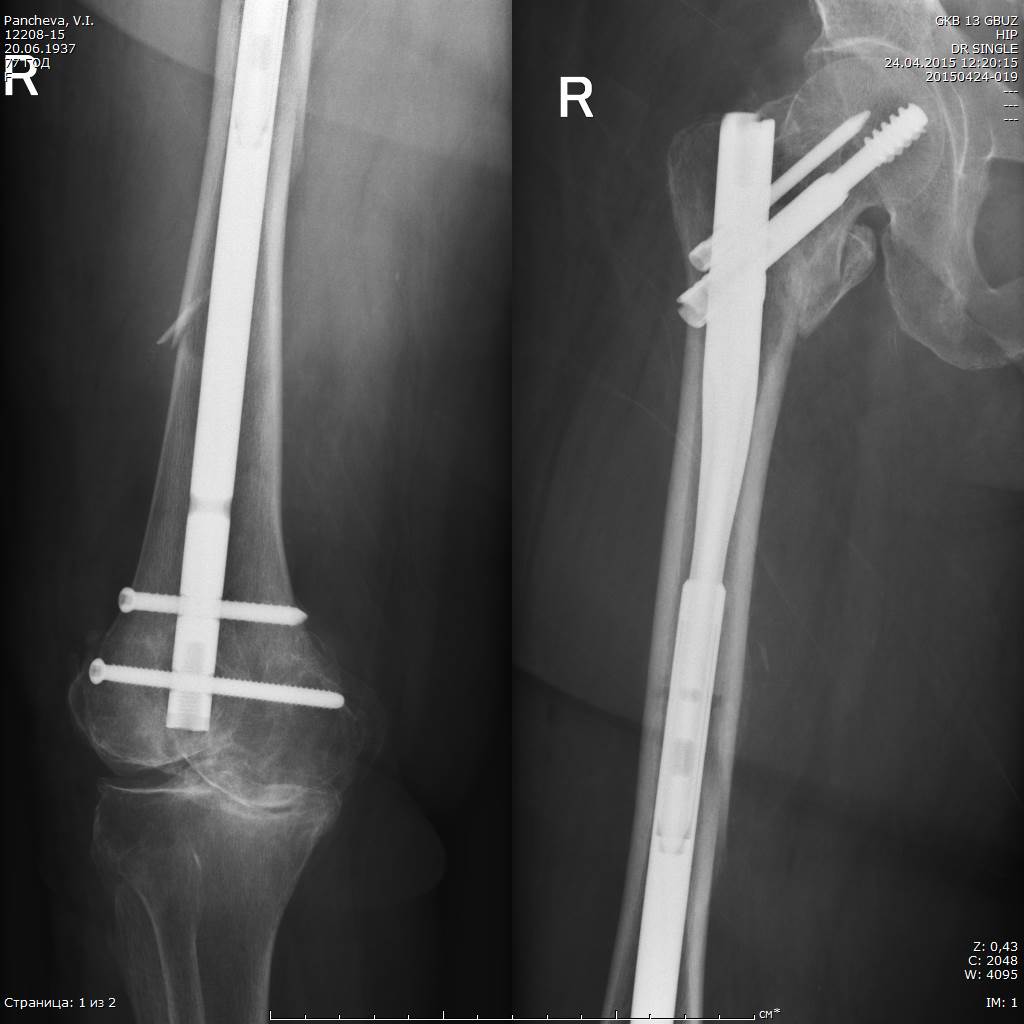

Имя     : 20150424-019_DR SINGLE _1.jpg

Имя     : 20150424-019_DR SINGLE _4.jpg